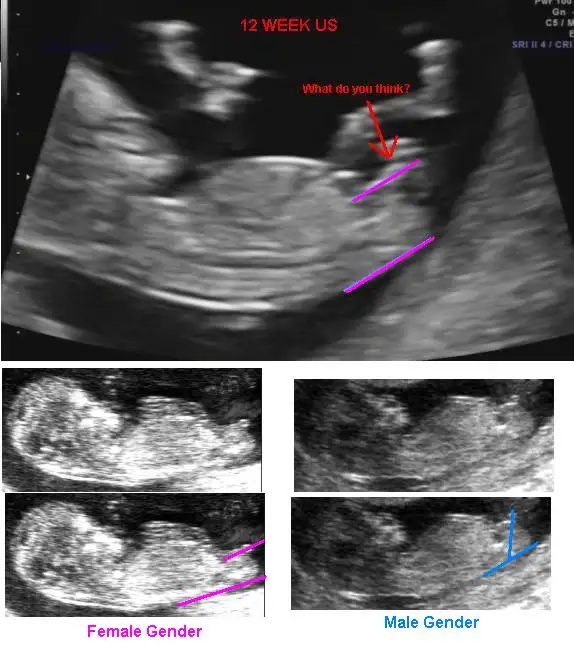

Bence suan hepimiz icin erken dojtorlar bile 12 haftadan once soylemio demekki gercekten 12 ye kadar olgunlasmasi gerekSuna bakın yorum yapın 11 12 13de daha belli olduğu için kadin onu istiyor benimki.mesela belli değil yapısal oaltakda net değil anlamadı. Aslında çok basit

Sende biliyon bu işi heraldeSuna bakın yorum yapın 11 12 13de daha belli olduğu için kadin onu istiyor benimki.mesela belli değil yapısal oaltakda net değil anlamadı. Aslında çok basit

ErkekkkkkkkkkkkkkkkkkkSuna bakın yorum yapın 11 12 13de daha belli olduğu için kadin onu istiyor benimki.mesela belli değil yapısal oaltakda net değil anlamadı. Aslında çok basit